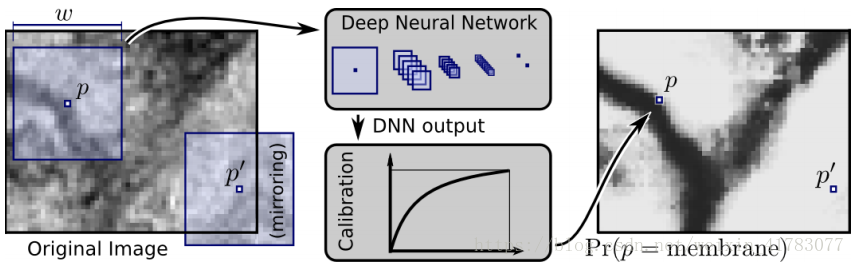

卷积神经网络不仅在处理医学影像辅助患者进行疾病诊断方面取得了巨大成功,在电子显微成像中对细胞膜分割方面同样有着积极的意义。文献[39][40]提出了基于卷积神经网络实现电子显微图像细胞膜自动分割的方法,方法中用卷积神经网络的监督训练去恢复patches中移除的中心像素标签,能够自动改善用于执行电子显微图像自动分割的细胞膜检测概率图。其中,patches是从细胞膜检测概率图中采样得到的,细胞膜检测概率图是通过分类器算法判断是否图像中的一个像素对应在细胞膜上得到。最后实验表明,相比于传统的机器学习算法,文献[39]方法性能有显著的提高,其结构如图15所示。

图15 深度神经网络监测细胞膜